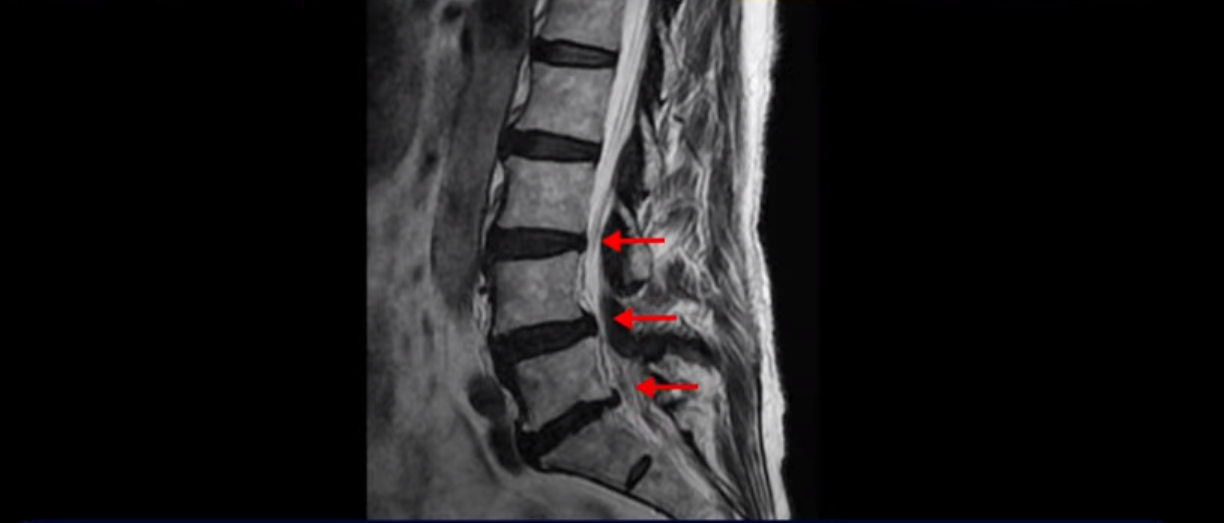

이분 MRI 보면서 설명드린 후 왜 이분처럼 발병한지 얼마 안된 협착증이 치료가 정말 빠르고 쉬운 건지 또 치료는 어떻게 하는 건지 자세히 설명 드리도록 하겠습니다.

MRI를 보면 척추 여러 마디가 퇴행되어 있고

척추관도 좁아져 있고

특히 왼쪽 신경가지가 빠져나가는 4번 5번, 5번 1번 추간공들이 많이 좁아져 있습니다.

그래서 이분은 몇 달 전부터 갑자기 왼쪽 엉덩이부터 발바닥까지 저리고 아픈 증상이 생겨서 걷기도 어렵고 무릎도 차고 시립니다. 그런데 왜 이렇게 얼마 전에 갑자기 발병한 협착증일수록 치료가 정말 빠르고 쉽다는 걸까요?

이분이 처음 아프게 된 건 작년 말입니다. 그런데 만일 이분이 아프기 전인 작년 초에 MRI를 찍었다면 지금 보시는 MRI와 많이 다를까요? 정답은 거의 차이가 없다입니다. 노화로 인해 신경 구멍이 좁아진 건 이미 오래 전에 벌어진 일입니다. 이렇게 신경 구멍이 좁아져 있는 채로 아무런 증상을 느끼지 않고 최소 5년에서 10년 이상 잘 산 것입니다. 이런 걸 잠복 협착이라고 합니다. MRI로 협착이 보이지만 아무런 증상이 없다는 뜻입니다.

그럼 왜 작년 말에 갑자기 아프게 된 걸까요? 바로 근육에 문제가 생겼기 때문입니다. 60세 넘어서 근육이 줄어들고 약해진 상태에서 무리한 일이나 운동 등으로 근육에 문제가 생기면 허리를 잘 지지하지 못하니까 신경이 자극되고 눌리는 증상이 생기는 겁니다. 신경 구멍이 좁아져 있으니까 근육에 문제가 생기면 신경 자극 증상이 더 쉽게 나타나는 겁니다. 이분은 영상에는 없지만 작년 겨울 스키를 타다 넘어졌다고 했습니다. 아마 그게 근육문제를 일으켰고 발병에 영향을 주었을 가능성이 높습니다.